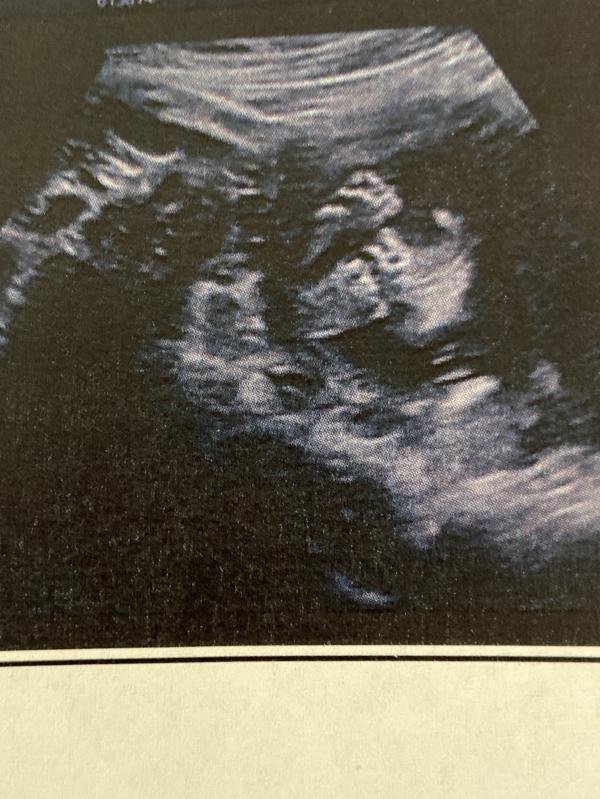

Этой ночью я почти не спала, ждала приема у врача. На узи малыш как будто был обижен на меня, все время отворачивался и врач долго не могла измерить все нужные параметры. Я была у Корж Л.В., она мне показалась добрейшей души человек, очень приятная и внимательная, если бы все врачи были такими то в мире было бы больше здоровых людей. Ковид не прошёл без последствий, заключения врача звучат очень страшно Пиелоэктазия, Вентикуломегалия мозга плода. Врач всячески успокаивала и просила не волноваться, сказала это может быть временным явлением и просто защитной реакцией малыша на недавне перенесенную болезнь 🤧. Я связалась с врачем который ведёт мою Беременность 🤰, жду заключения от неё и рекомендаций что делать дальше. Сердце не на месте. Смотрю на фото узи и сердце разрывается, эта крошка никому ничего в этой жизни не сделала плохого, а уже страдает. Мир не справедлив! На фото наши ножки, незнаю почему ну вот это фото прям стало любимым)